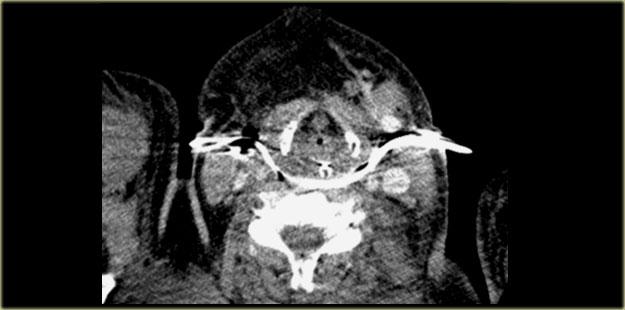

Áp-xe sau hầu

Bên trái là hình ảnh CT cắt ngang có tiêm thuốc cản quang của một trẻ nhũ nhi bị sốt.

Trẻ không thể nuốt được.

Tổn thương bệnh lý này nằm trong khoang sau hầu.

Các cơ trước cột sống bị đẩy về phía thân đốt sống.

Nếu đây là tổn thương nằm trong khoang cạnh cột sống, các cơ này sẽ bị đẩy ra phía trước.

Khoang sau hầu bị giãn rộng và chứa nhiều ổ dịch có tỷ trọng dịch.

Rõ ràng đây là tình trạng nhiễm trùng sau hầu với nhiều ổ áp-xe.

Đây là tình huống cấp cứu vì các ổ áp-xe sẽ tiếp tục lan rộng và có thể gây tắc nghẽn đường thở.

Thông thường, các ổ áp-xe sâu này cần được dẫn lưu phẫu thuật.

Bên trái là hình ảnh của một bệnh nhân người lớn bị áp-xe sau hầu sau khi được dẫn lưu phẫu thuật.

Các ống dẫn lưu chạy từ trái sang phải xuyên qua khoang sau hầu.